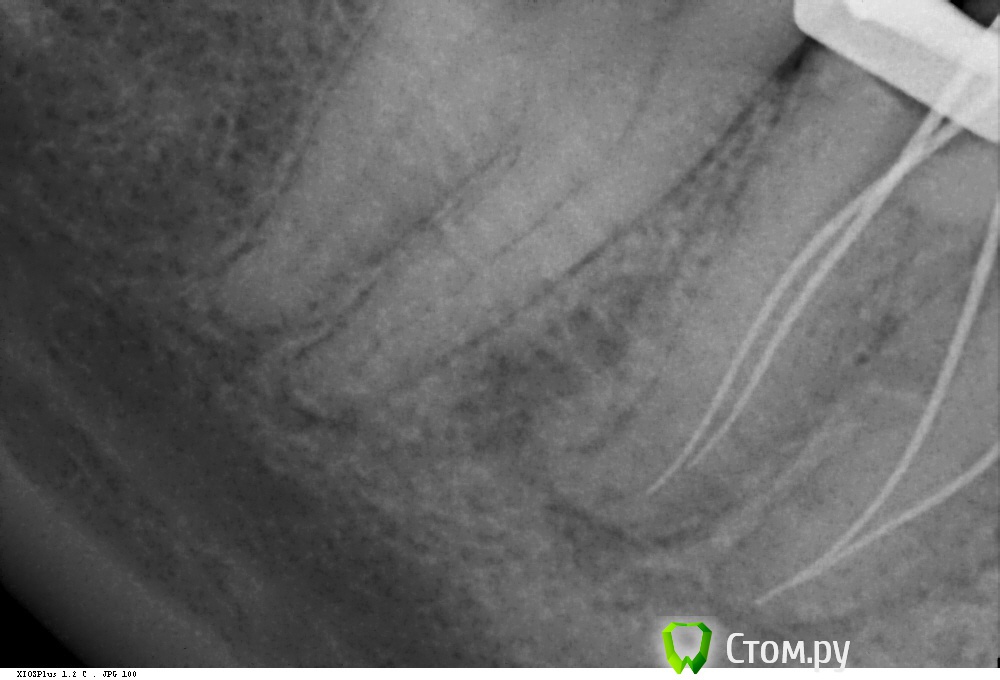

Shaid Опубликовано 29 января, 2014 Автор Поделиться Опубликовано 29 января, 2014 (изменено) Рис.1 Пульпит 2.5. Ничего необычного нет, просто понравился снимок) Возможно, кому-то покажется, что каналы перерасширены?Рис.2,3 Тоже пульпит пятерки. Тот случай, когда спредер залезает в канал, а 15 штифты - нет, гнутся , в результате чего картинка вызывает ассоциации, будто в каналы засунули по две дренажной трубки из хирургии. Изменено 29 января, 2014 пользователем Shaid Ссылка на комментарий